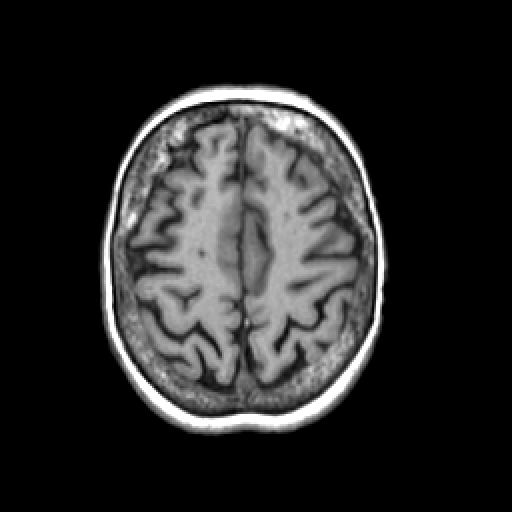

T1-weighted structural MR: Slice 40

Slice 40